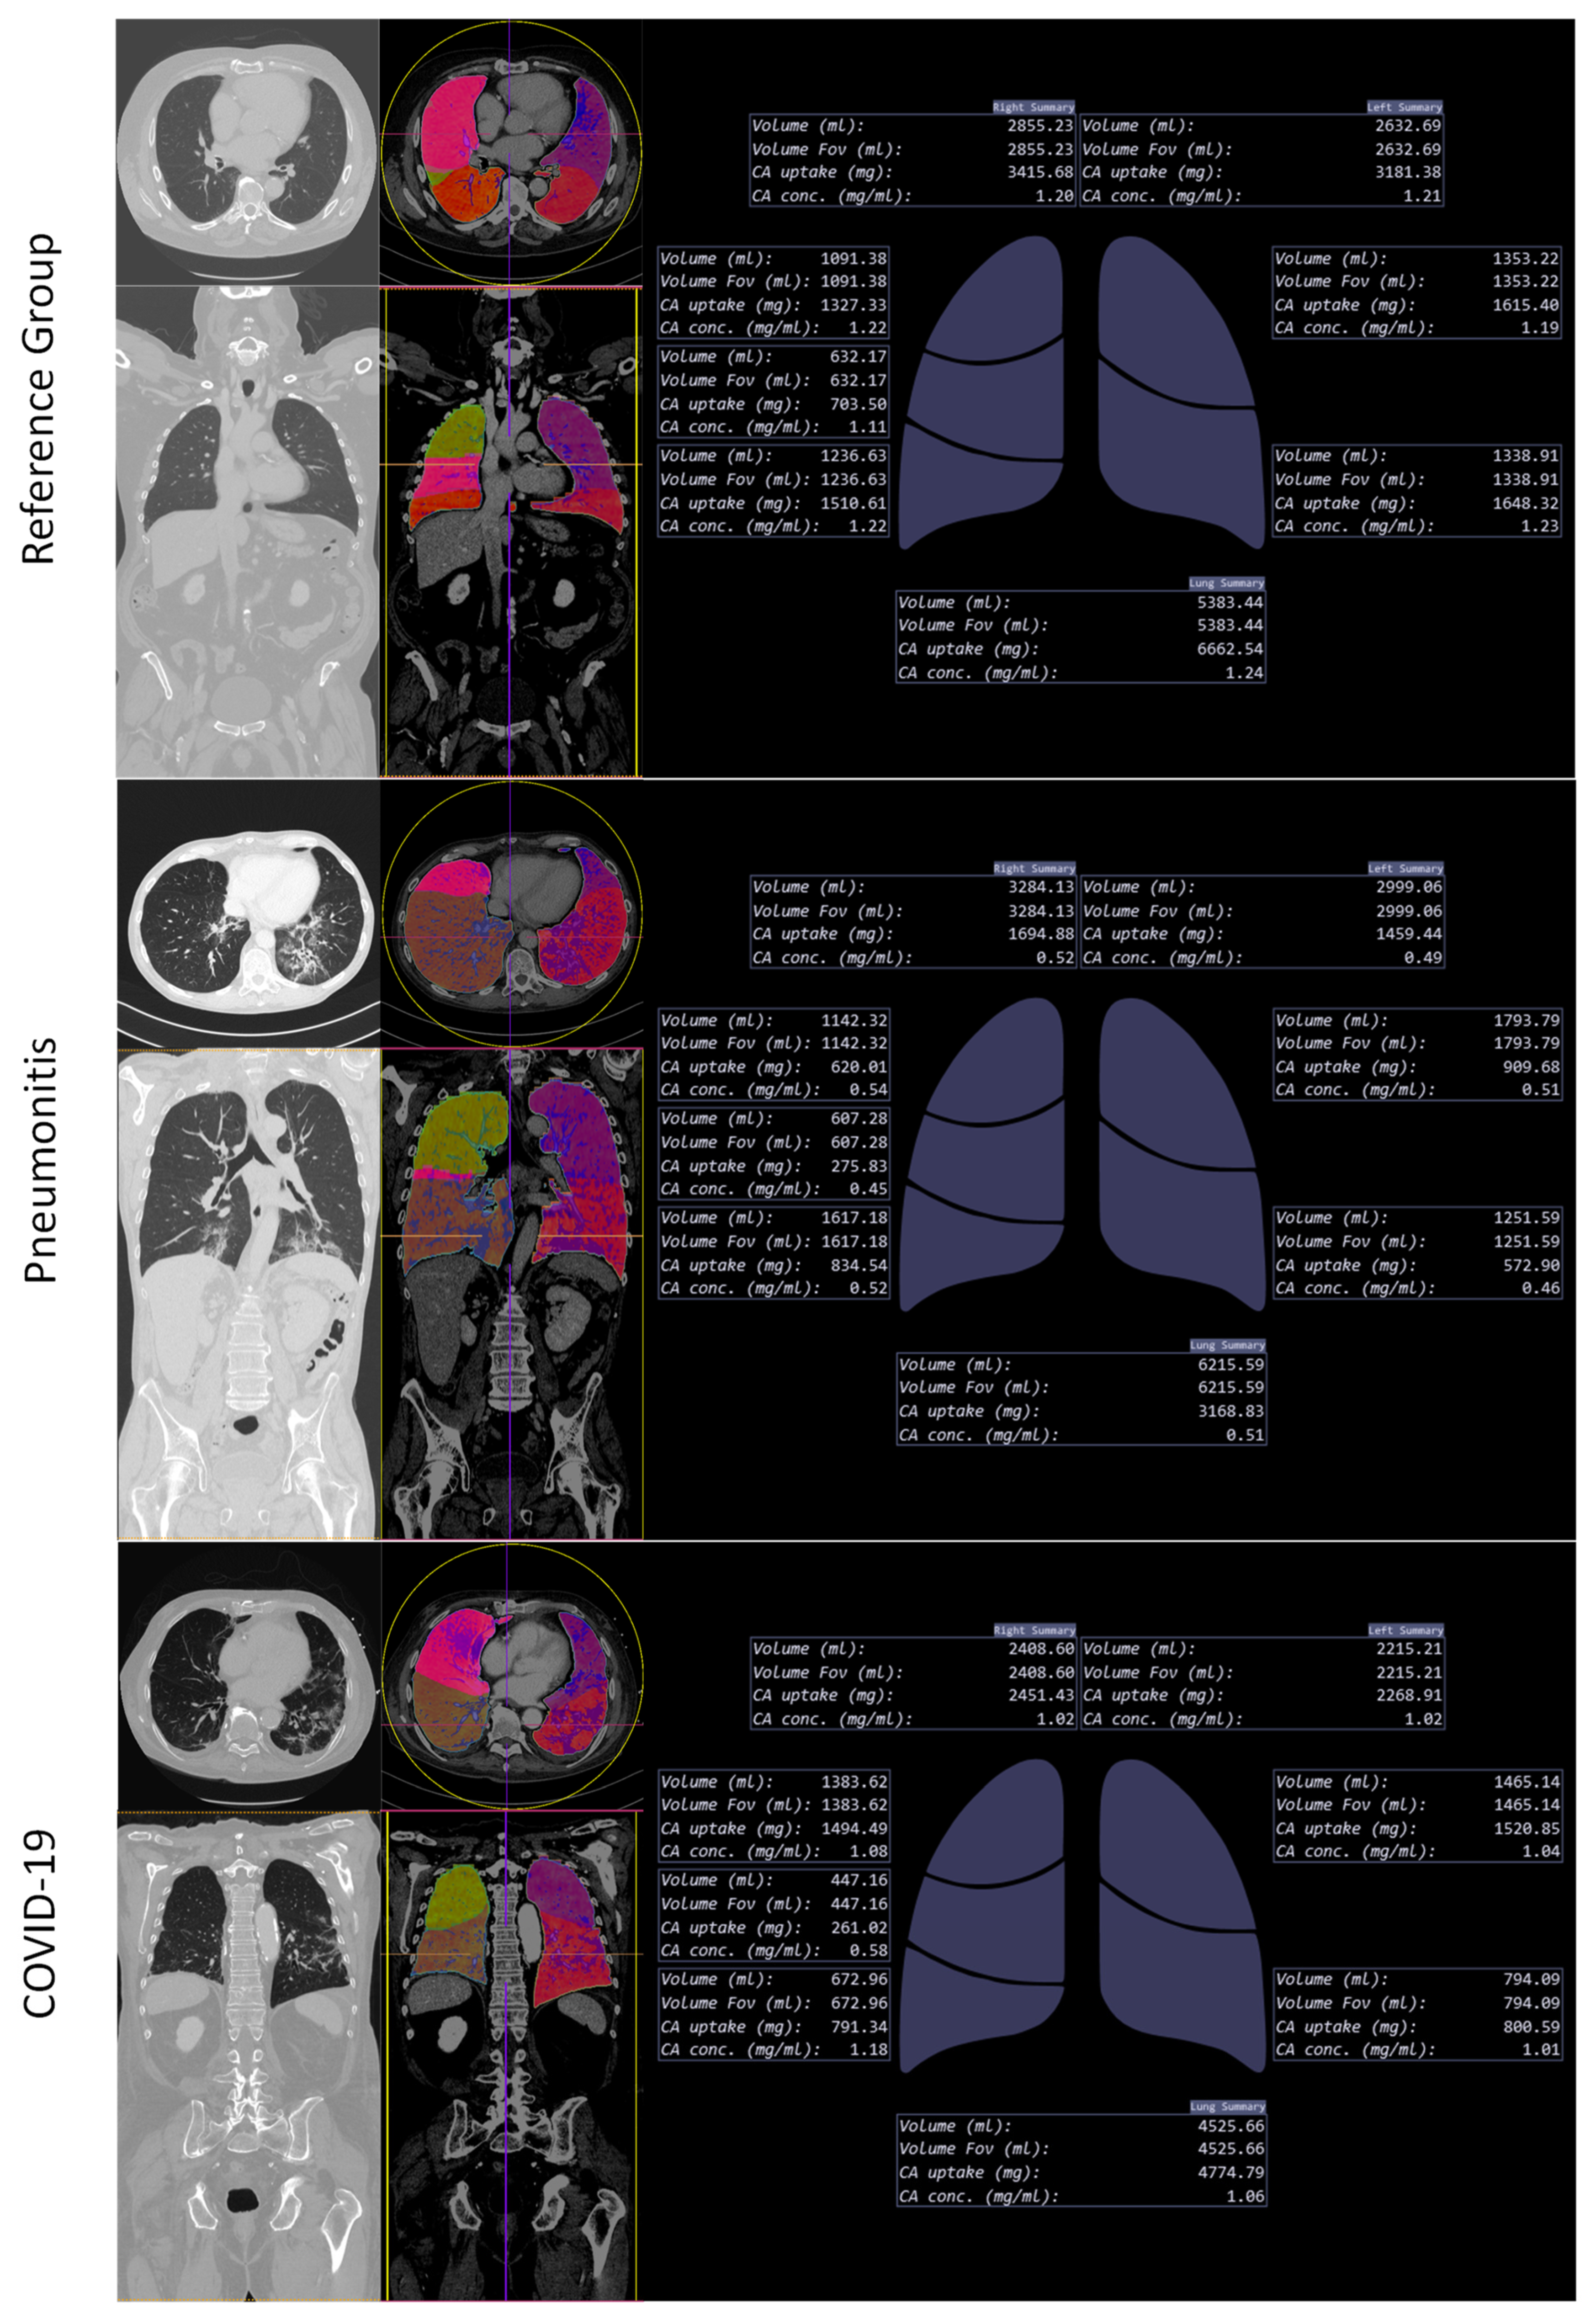

2.4. Lung Segmentation and Perfusion Analysis

3.2.2. Analysis of AI-Based Lung Segmentation